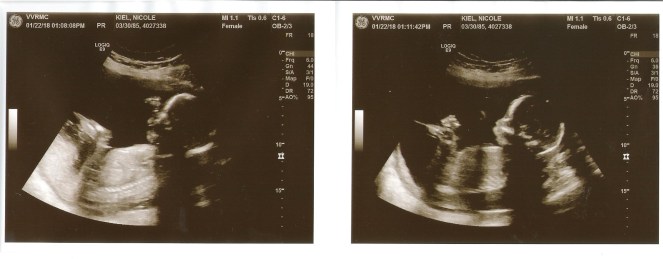

Looking forward to: Our next OB appointment — we’ll be talking about the anatomy scan we had done, and I’m eager to know if everything is looking normal and healthy.